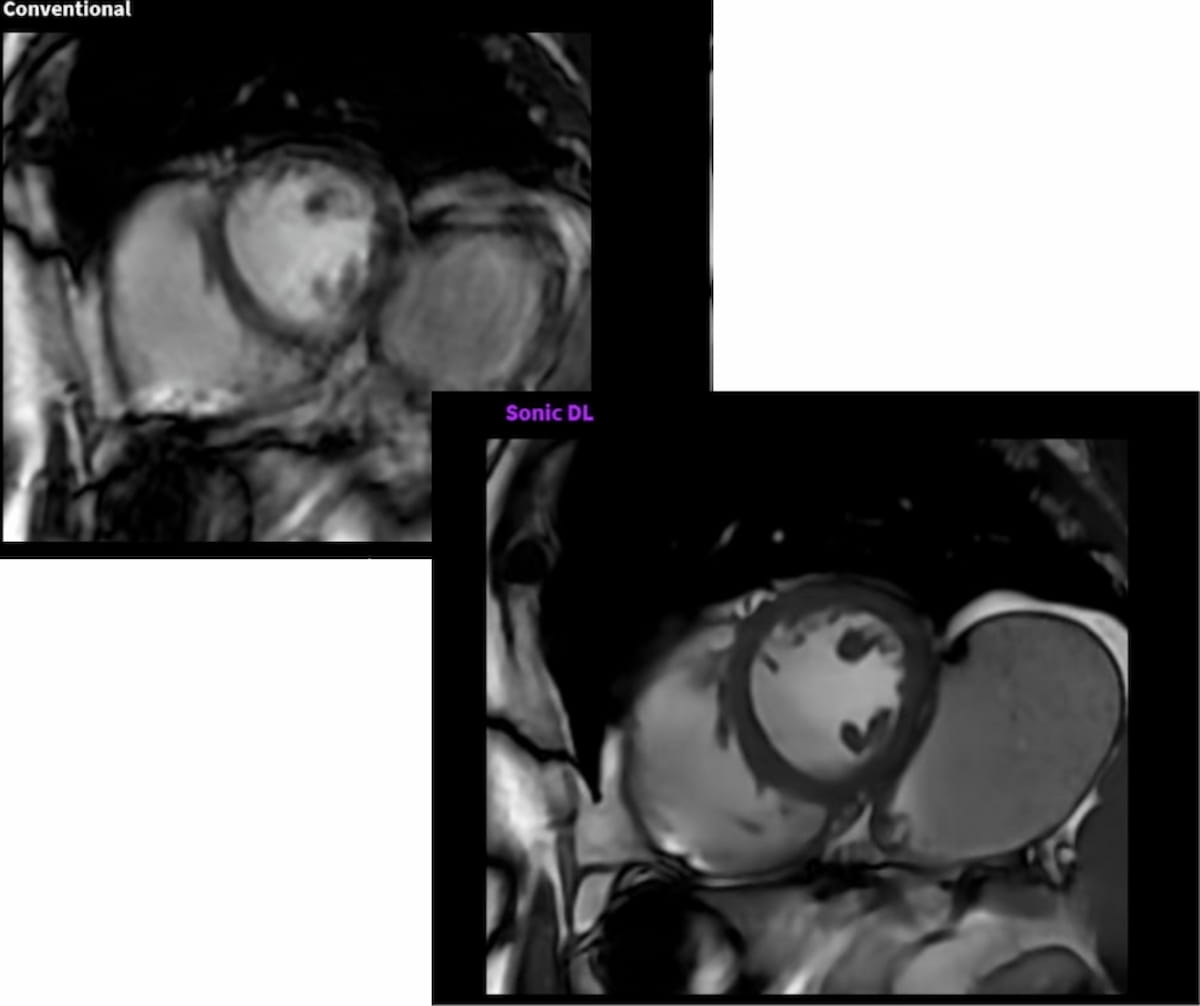

Conditional use of full-body magnetic resonance imaging (MRI) is reportedly permitted for patients using any of the models for the remede® System, an implantable nerve stimulation therapy indicated for the treatment of adults with moderate to severe central sleep apnea.